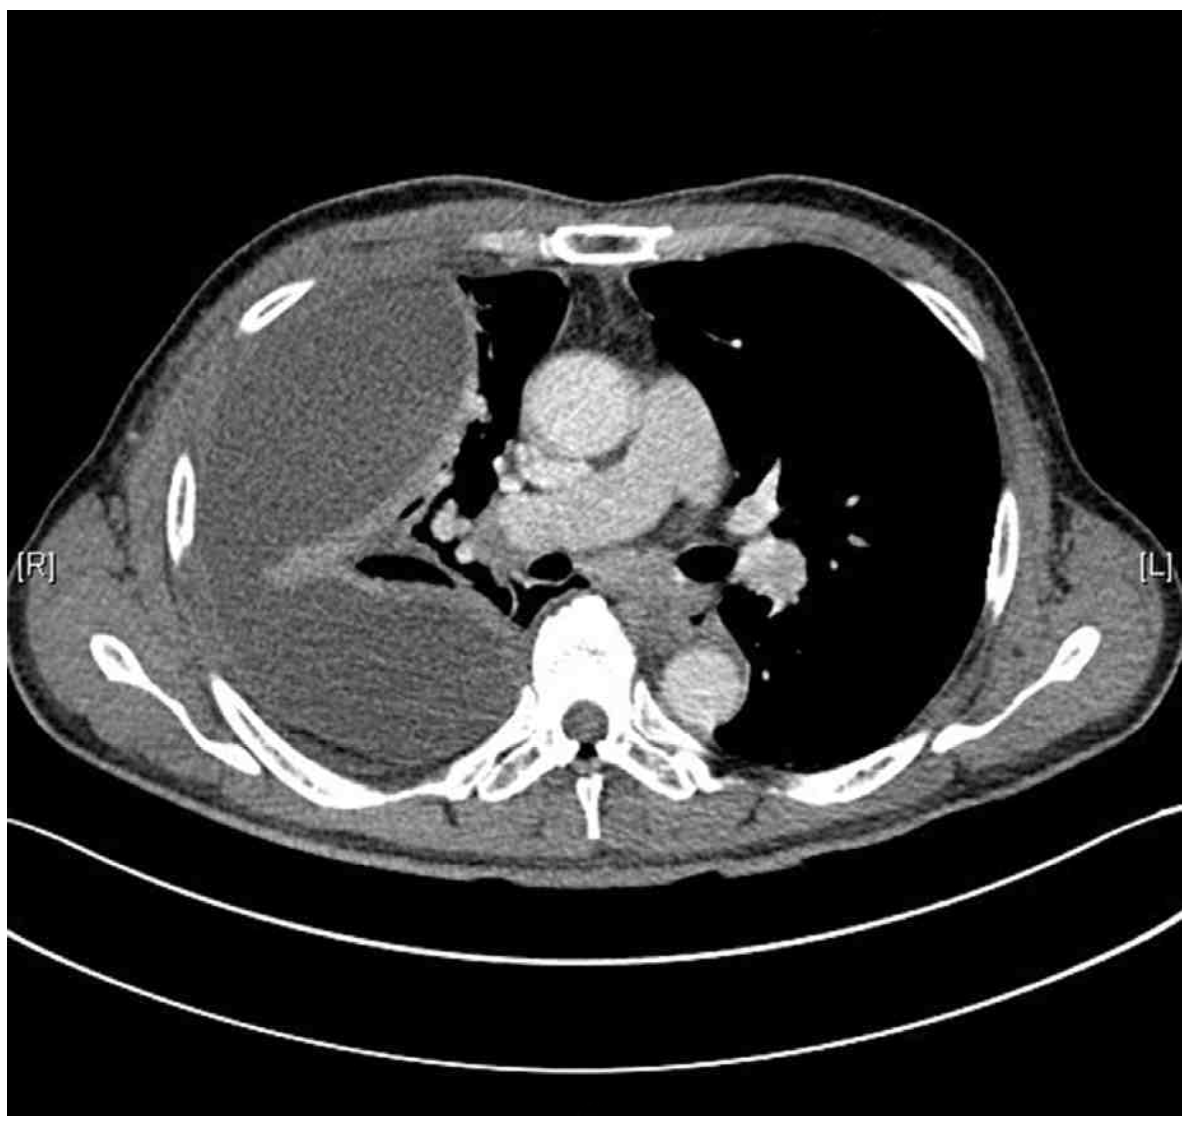

69세 남자가 1주 전부터 열이 나고 오한이 들어 병원에 왔다. 1일 전부터 가슴통증이 심해지고 숨이 찼다고 한다. 당뇨병으로 치료 중이고 비흡연자이다. 혈압 136/80 mmHg, 맥박 102회/분, 호흡 24회/분, 체온 38.6°C이다. 오른쪽 가슴에서 호흡음이 감소되어 들린다. 가슴 X선사진과 가슴 컴퓨터단층촬영 사진이다. 검사 결과는 다음과 같다. 검사는?

CXR: Rt. pleural effusion

CT: Rt. pleural effusion, loculated

• CXR상 우측 흉강의 pleural effusion을 관찰할 수 있으며 chest CT에서도 해당 부위의 loculated pleural effusion을 확인할 수 있다. 현재 발열, 빈맥, 빈호흡 및 CRP elevation, neutrophil-dominant leukocytosis 등으로 보아 세균성 감염이 원인으로 추정되며, 환자가 당뇨병으로 치료 중이라는 점에서 감염에 취약한 상태일 가능성을 배제할 수 없다.

• CXR 및 chest CT를 통해 흉수의 존재를 확인하였으므로 진단적 흉막천자를 통해 그 원인을 감별하여야 한다.